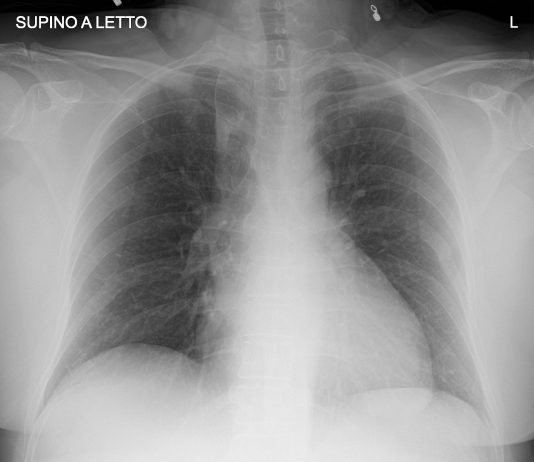

57-year-old male

patient admitted to the ED with fever, cough and...